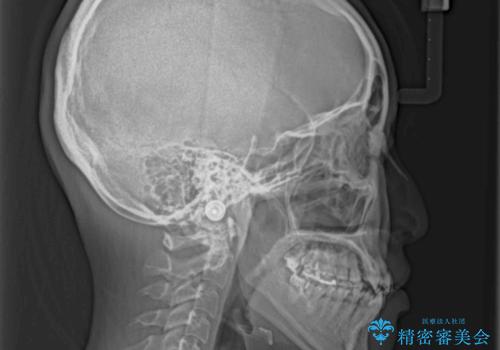

- 前歯のデコボコとクロスバイトを治したいとのことで来院された患者様です。

上下顎ともに歯列全体の側方拡大とIPR(歯と歯の間を削る)によってデコボコとクロスバイトが解消するように設計し、インビザラインにより治療を行うこととしました。

下顎骨の左側への骨格的なずれが強く、上下の正中の位置合わせや奥歯の咬み合わせ構築に苦労しました。